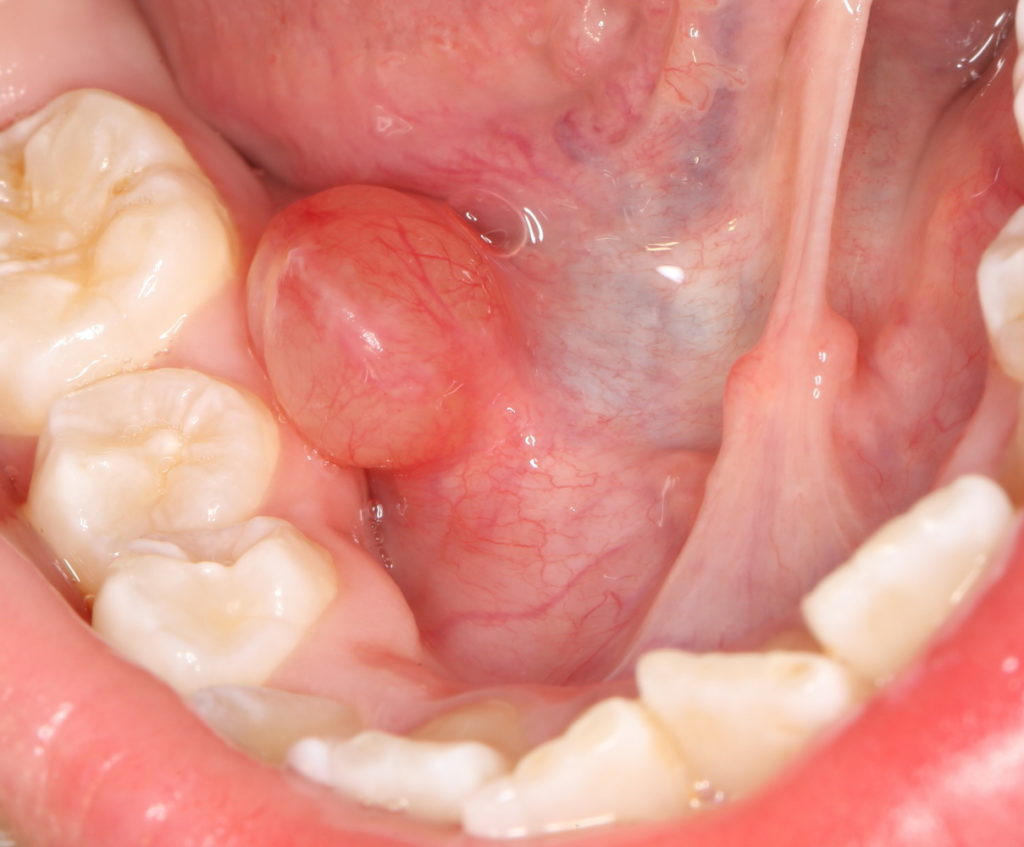

Подъязычное образование в виде мягкой прозрачной субстанции именуется ранула. Слизистая киста может достигать значительных размеров, мешая поглощению пищи. Единого мнения относительно причин образования кист во рту не существует, а вот разногласий относительно лечения не возникает. Единственный метод борьбы с образованием – хирургическое удаление ранулы.

Если говорить о локализации кист, то называют поверхностные и ныряющие ранулы. Первые имеют четкую форму и размеры, поскольку локализуются непосредственно на слизистой. Вторые скрыты за поверхностными тканями. Если ранула сформировалась в глубине слизистой оболочки полости рта, то ее можно спутать с увеличенным лимфатическим узлом.

Основным симптомом заболевания является шарообразное формирование в подъязычной области. Оно не болит, но мешает во время приема пищи. При пальпации можно обнаружить, что содержимое образования имеет жидкую форму. У детей грудного возраста возникают проблемы с сосанием, что сказывается на весе и темпах развития. Во взрослом возрасте ранула становится причиной дефекта речи.